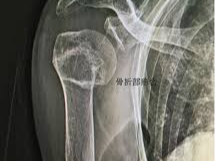

상완골 골절이란 무엇인가

상완골은 어깨부터 팔꿈치까지 이어지는 긴 뼈로, 어깨관절과 팔꿈치관절을 연결하는 핵심 구조입니다. 이 부위가 골절되면 단순한 통증을 넘어서 팔의 움직임 자체가 제한되며 일상생활에 큰 불편을 초래합니다.

- 간부 골절: 중간 뼈 부분 골절

이처럼 상완골 골절은 위치에 따라 치료 방법과 회복 속도가 크게 달라집니다.